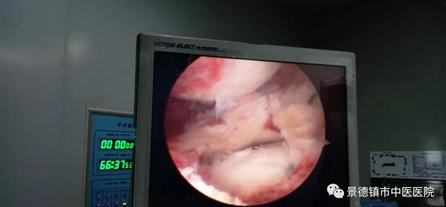

半月板“桶柄樣”撕裂

前交叉韌帶斷裂